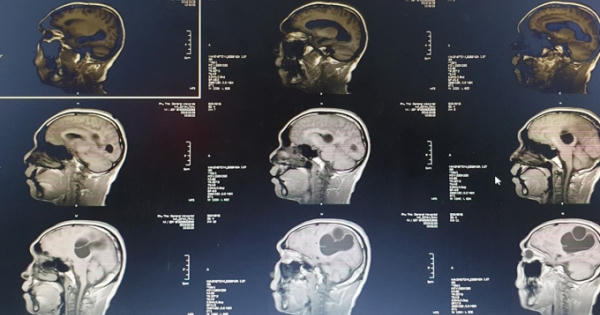

Nhiễm ấu trùng sán là bệnh lý đang lan rộng và gây "hoang mang" ở nước ta giai đoạn vừa qua với hơn 200 bệnh nhi bị nhiễm. Căn bệnh này nếu không được chữa trị kịp thời sẽ dẫn tới những biến chứng vô cùng khôn lường!

Bệnh viện Đa khoa tỉnh Phú Thọ vừa cấp cứu thành công cho Hà Đăng N. (40 tuổi, trú tại Tân Sơn, Phú Thọ) có sán làm tổ trong não.